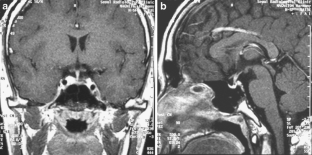

This case involves an 18-year-old man who presented with abnormal behavior, impairment in recent memory, and emotional change. Five years ago, he received five cycles of chemotherapy using cisplatin and ectoposide and 24G of local radiotherapy for clinical diagnosis of suprasellar germinoma in another hospital. The tumor was then completely resolute. Magnetic resonance imaging in our hospital revealed a large fatty mass located primarily in the septum pellucidum and some portions of the corpus callosum; a heterogeneous enhancing tumor was observed in the surrounding area. The second tumor was completely removed. The histological diagnosis was mixed GCTs containing the component of a germinoma and a mature teratoma.

Fig. 2